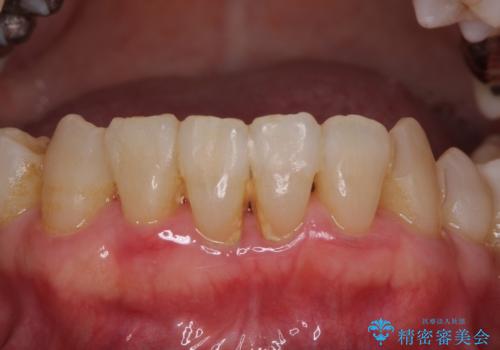

数多くの外科処置を行ったため、治療期間は長期間となりました。

一方、外科処置をしっかりと行ったことで、歯周病の状態は改善され、安定した状態にしあげることができました。